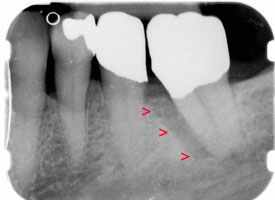

Durch eine systematische Parodontalbehandlung und einem kleinen Eingriff, um den Knochen an dieser Stelle aufzubauen, konnte der Knochendefekt ganz eliminiert werden und dadurch der Zahn erhalten werden.